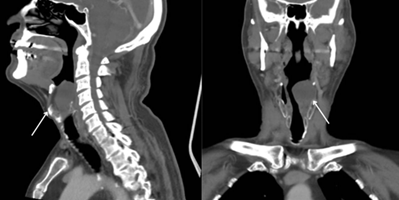

compression. A computed tomography scan showed a 3.7 × 3.7 cm heterogeneous

hypodense formation in the left paraglottic region, significantly reducing the

glottic and supraglottic airway column7,8. Referred to Head and Neck Surgery,

Figure 1: Computed tomography of the neck, showing a hypodense formation in the fat of the left paraglottic space measuring 3.7 x 3.7 cm, causing local bulging with reduction of the airway column in the glottic and supraglottic larynx